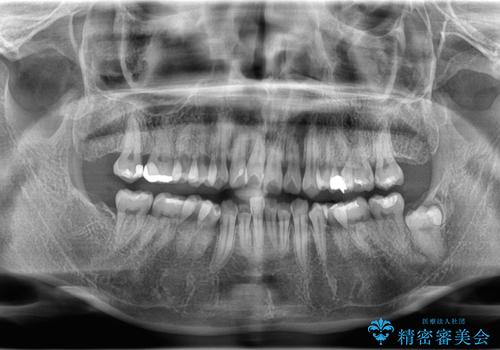

1. 【埋伏智歯と埋伏智歯の過剰歯の抜歯】埋まっている親知らず2本の抜歯の治療前